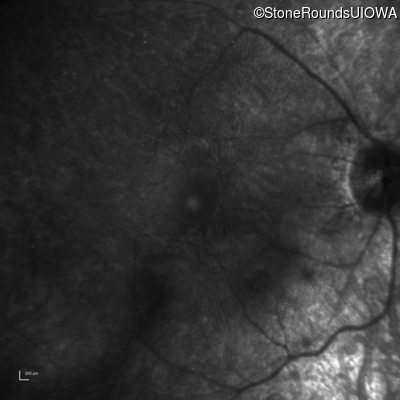

Infrared Fundus Photograph - Right - 20/20 sc

Exemplar

Infrared Fundus Photograph - Left - 20/30 sc